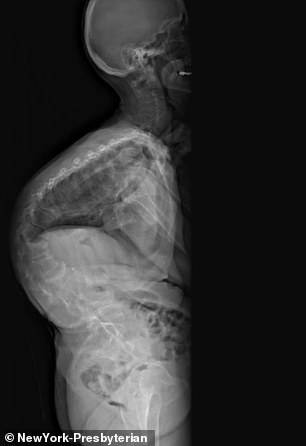

"جان" 19 ساله با اسکولیز خطرناکی که داشت نزدیک بود ستون فقراتش را از دست دهد در نهایت توانست پس از 17 سال با کمری به شکل علامت سوال است بایستد ؛ جان وقتی پنج ساله بود ، ستون فقراتش شروع به خم شدن در دو شکل مختلف کرد. این بیماری چنان به شدت کمرش را چرخاند که اسکلتش در خطر خرد شدن و تخریب اندام های داخلی اش قرار داشت. "جان" پس از سپری کردن دوران کودکی و بیشتر دوران نوجوانی اش، با این درد مشقت بار جراحی اصلاحی 13 ساعته داشت که در طی آن پزشکان به سختی و البته با حساسیت خاصی ستون فقرات او را صاف کردند.

جان دو نوع ناهنجاری نخاعی دارد:اسکولیز و کفیوز که اسکولیز معمولا از این دو هم بیشتر شناخته شده و باعث می شود ستون فقرات شکل'S' بگیرد. کفیوزدر میان جوانان غیر عادی است اما در میان افراد مسن شایع است و اصطلاح گوژ پشت نامیده می شوند، این بیماری باعث می شود که او دچار مشکلی شود که اغلب ظاهری را ایجاد می کند که یک فرد به جلو خم می شود. در این مورد، دو بیماری پشت سر هم برای هل دادن و کشیدن قسمت های مختلف ستون فقرات او به سمت جلو و چپ و راست حرکت می کردند - انگار که استخوان های او آلومینیوم بودند.

زمانی که او دکتر لاورنس را در نیویورک دید، ستون فقرات او در 140 درجه انحنا پیدا کرد و کمر "جان" به جلو خم شده بود و به سمت راست متمایل می شد ؛ تیم دکتر به خانواده اش گفت اسکلت جان در یک ساعت خم شده است و همین که اتفاق افتاد فشار زیادی روی قلب و سینه اش آمد.